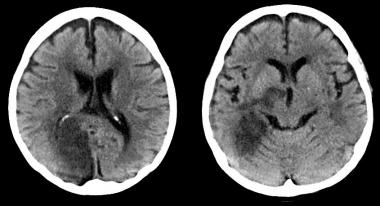

Cabezazos en el fútbol y síntomas neurológicos

Tanto el cabeceo de la pelota como los traumatismo involuntarios durante el juego se asociaron a un aumento de síntomas neurológicos moderados a severos. Neurology, 1º de febrero de 2017